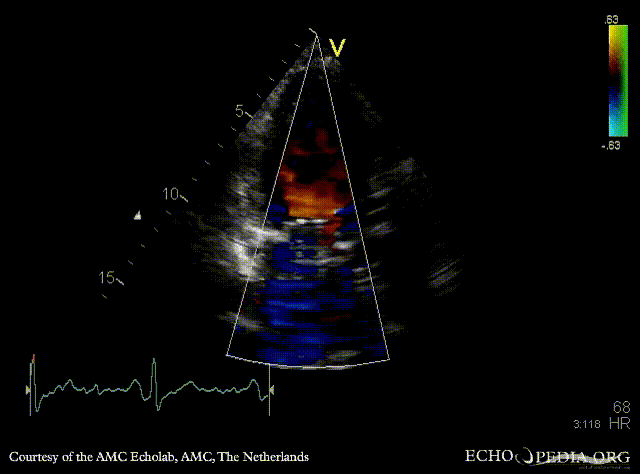

E00596.gif E00597.gif

PLAX: mechanical mitral valve prosthesis, dilated left ventricle and left atrium PLAX with Color Dopler: no mitral regurgitation